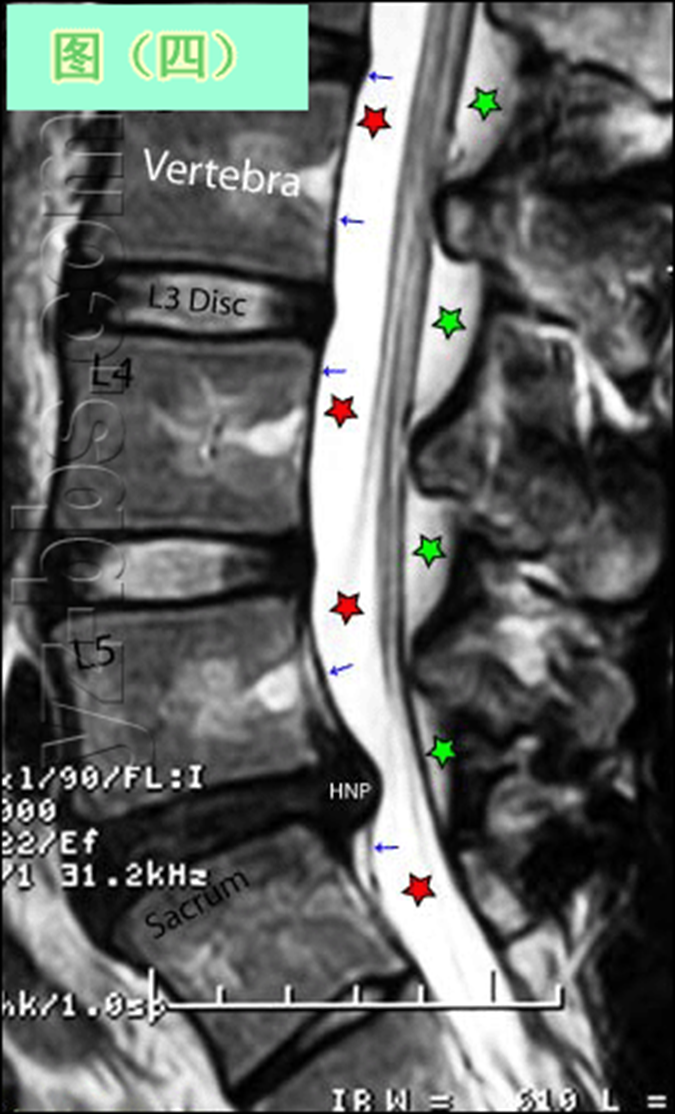

后纵韧带(PLL小蓝箭头)在图像中表现为沿着每个椎体及椎间盘后缘垂直向下的黑线。有意思的是,尽管此病人有一个9mm的椎间盘突出(HNP),骨质有一定的翘起,在椎间盘平面以上可见髓核物,但后纵韧带仍然包容着突出的髓核物而没有游离出。这种情况在学术上被称作一个大的包容性椎间盘突出。

硬膜囊(红星)表现为“超白色”结构,填充在椎体后方的中央椎管内。此囊袋内有可自由浮动的由运动神经纤椎及感觉神经纤维共同组成的脊神经根(马尾)。

黄韧带(绿星)位于每个椎骨之间,增强脊柱的稳定性。此结构可变大或增厚,助长年长者易患的中央型椎管狭窄的形成。